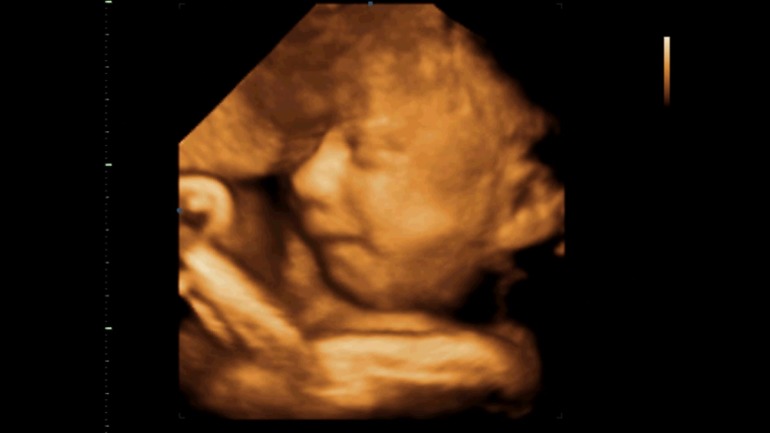

16.12.2013 года в 9.45 родился наш сынок Данечка. Вес 3500, рост 53 см., 9/10 по Апгар путем КС на 42й неделе.